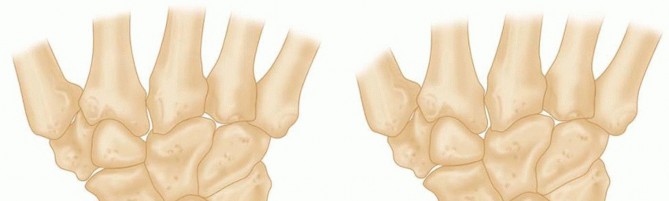

The exact etiology of Kienböck disease remains a subject of intense academic debate, but it is universally accepted as a multifactorial process. The prevailing consensus points toward a complex interplay between vulnerable vascular anatomy, adverse biomechanical loading, and repetitive microtrauma. The lunate sits at the apex of the proximal carpal row, acting as the keystone of the wrist. When subjected to repetitive compressive and shear forces—particularly in the setting of negative ulnar variance—microfractures develop within the trabecular architecture of the bone. Unlike other bones with robust collateral circulation, the lunate struggles to heal these microfractures, leading to localized edema, increased intraosseous pressure, and subsequent venous congestion.

This venous hypertension initiates a vicious cycle. As intraosseous pressure rises, it eventually exceeds capillary perfusion pressure, leading to arterial ischemia and osteocyte death. The necrotic trabeculae lose their structural integrity, making the lunate highly susceptible to macroscopic collapse under the normal physiological loads of daily activities. Current histopathological studies suggest that the disease may stem more fundamentally from this venous outflow obstruction and intraosseous vascular congestion than from primary arterial insufficiency. This congestion, combined with stress fractures in the proximal lunate adjacent to the radial articular surface, leads to the predictable, progressive collapse we observe radiographically.

This unique vascular anatomy explains why even minor, repetitive trauma or altered biomechanics can trigger catastrophic AVN. The proximal pole of the lunate, which articulates directly with the lunate fossa of the distal radius, is particularly vulnerable, as it is the furthest point from the dorsal and volar vascular entry zones. Our surgical goal with the osteotomy is to create a more favorable mechanical environment, drastically reducing the compressive and shear forces across this ischemic proximal pole, thereby allowing the tenuous vascular supply a chance to recover and initiate creeping substitution.

However, when a patient exhibits negative ulnar variance—where the ulna is anatomically shorter than the radius—this delicate load-sharing ratio is severely disrupted. Biomechanical studies have shown that even a 1 to 2 mm negative variance can shift the load distribution such that the radius bears up to 95% of the transcarpal forces. This disproportionately high load is concentrated directly across the radiolunate joint. The lunate is subjected to immense shear and compressive forces, particularly at its radial aspect, where its articulation with the rigid lunate fossa of the distal radius is far less compliant than its articulation with the thicker, shock-absorbing TFCC on the ulnar side.

The radial shortening osteotomy directly and elegantly addresses this biomechanical imbalance. By surgically shortening the radius by a meticulously calculated 2 to 3 millimeters, we effectively "level" the joint. This intervention decreases joint compression forces at the radiolunate joint and redistributes them ulnarward to the ulnolunate joint and the TFCC. Furthermore, shortening the radius relatively lengthens the extensor and flexor musculotendinous units crossing the wrist joint. This "de-tensioning" effect further diminishes the overall static compressive forces acting on the carpus, providing a significant biological advantage over ulnar lengthening procedures, which do not offer this musculotendinous relaxation.